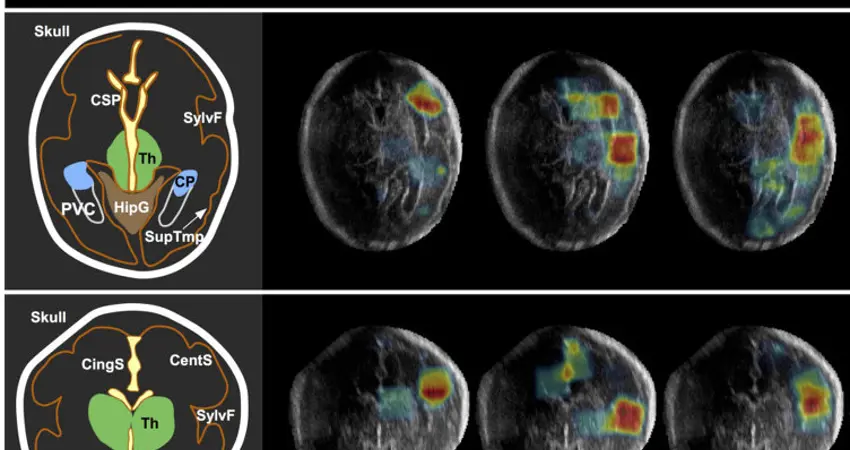

“As such, I was specifically interested in developing efficient machine learning algorithms which could analyse images on mobile devices, allowing automated ultrasound analysis in remote locations.” The team’s research, which focuses on automated image analysis of the fetal brain, has the potential to revolutionise prenatal healthcare. It could help to diagnose conditions such as malnutrition and fetal alcohol syndrome far earlier than would otherwise be possible, ensuring that medical attention can be received in time.

Dr Namburete and her team are supported by a Global Challenges Research Fund from the Royal Academy of Engineering. Their research focuses on developing computational algorithms to enhance the diagnostic value of neurosonographic images. Through their work, the team aims to establish ultrasound as a cost-effective tool for early assessment of brain maturation during pregnancy.